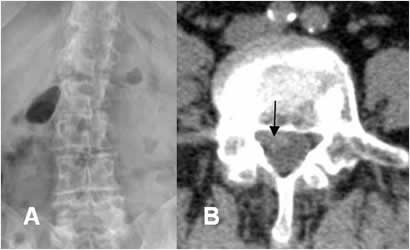

Fig 17. Hernia de disco.

A: Rx AP y B: TAC axial. Desviación lumbar derecha. Este hallazgo es secundario al espasmo muscular, ocasionado por una hernia paramediana.